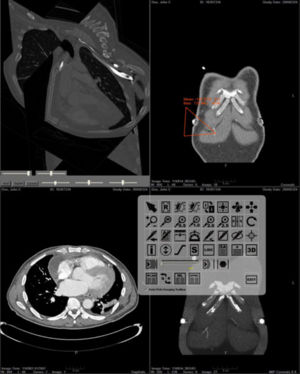

MRI-Only Based Radiotherapy Treatment Planning for the Rat Brain on a Small Animal Radiation Research Platform (SARRP)

Publication: PLoS One. 2015 Dec 3;10(12):e0143821. PMID: 26633302 | PDF Authors: Gutierrez S, Descamps B, Vanhove C. Institution: Medical Image and Signal Processing Group, Ghent University-iMinds Medical IT department, Ghent, Belgium. Background/Purpose: Computed tomography (CT) is the standard imaging modality in radiation therapy treatment planning (RTP). However, magnetic resonance (MR) imaging provides superior soft tissue contrast, increasing the precision of target volume selection. We present MR-only based RTP for a rat brain on a small animal radiation research platform (SARRP) using probabilistic voxel classification with multiple MR sequences. Six rat heads were imaged, each with one CT and five MR sequences. The MR sequences were: T1-weighted, T2-weighted, zero-echo time (ZTE), and two ultra-short echo time sequences with 20 μs (UTE1) and 2 ms (UTE2) echo times. CT data were manually segmented into air, soft tissue, and bone to obtain the RTP reference. Bias field corrected MR images were automatically segmented into the same tissue classes using a fuzzy c-means segmentation algorithm with multiple images as input. Similarities between segmented CT and automatic segmented MR (ASMR) images were evaluated using Dice coefficient. Three ASMR images with high similarity index were used for further RTP. Three beam arrangements were investigated. Dose distributions were compared by analysing dose volume histograms. The highest Dice coefficients were obtained for the ZTE-UTE2 combination and for the T1-UTE1-T2 combination when ZTE was unavailable. Both combinations, along with UTE1-UTE2, often used to generate ASMR images, were used for further RTP. Using 1 beam, MR based RTP underestimated the dose to be delivered to the target (range: 1.4%-7.6%). When more complex beam configurations were used, the calculated dose using the ZTE-UTE2 combination was the most accurate, with 0.7% deviation from CT, compared to 0.8% for T1-UTE1-T2 and 1.7% for UTE1-UTE2. The presented MR-only based workflow for RTP on a SARRP enables both accurate organ delineation and dose calculations using multiple MR sequences. This method can be useful in longitudinal studies where CT's cumulative radiation dose might contribute to the total dose. |

Illustration of a CB-CT and five MR images of the same animal. a) Coronal CB-CT image and (b)-(f) biased field corrected and masked coronal MR images using a T1-weighted (b), T2-weighted (c), ZTE (d), UTE1 (e) and UTE2 (f) sequence. All CB-CT images were first co-registered using 3D Slicer version 3.6.3 by rigid body transformations using normalized mutual information. |